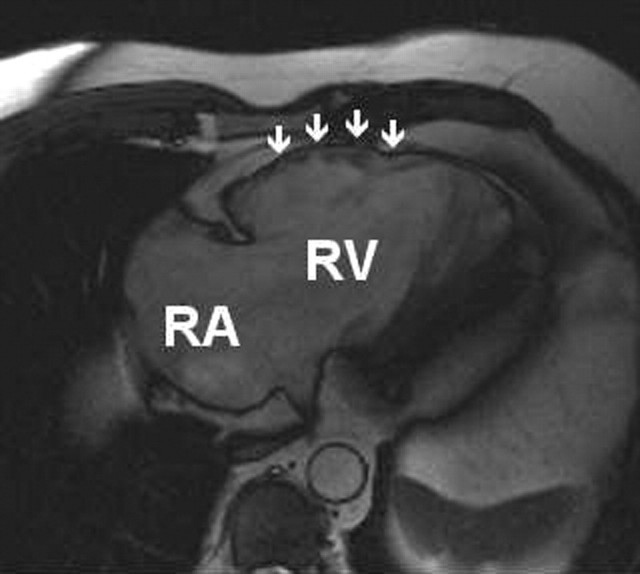

Figure 2.

Cardiac MRI showing dilated right atrium (RA) and right ventricle (RV) with thinning of the RV free wall. Aneurysmal pockets (marked) are also seen

On transfer the patient was in sinus rhythm (Figure 1b). Coronary angiography and ventriculography showed no abnormality. On echocardiography, left ventricular size and function were normal but the right atrium and right ventricle were dilated with impaired function. On MRI (Figure 2) the right ventricular free wall appeared thin, with the suggestion of small aneurysmal pockets and fatty infiltration. These findings were consistent with a diagnosis of arrhythmogenic right ventricular dysplasia (ARVD). The patient was treated with a beta-blocker and an angiotensin converting enzyme inhibitor and fitted with an implantable cardiac defibrillator. The amiodarone was discontinued because of previous thyroid dysfunction when taking this drug.

The electrocardiographic findings shown in Figure 1b are typical, with left axis deviation, partial right bundle branch block, T wave inversion in leads V1 to V3, and post-excitation potentials called epsilon waves.5 The record made during tachycardia shows a left bundle branch block morphology and inferior QRS axis consistent with an origin near the right ventricular outflow tract. Together with the MRI evidence of right ventricular dysfunction and fatty infiltration of the myocardium6 these features are diagnostic for ARVD.4